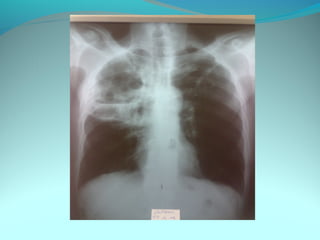

Opacité occupant la partie externe du 1/3 infer du poumon droit

dense et homogene ovalaire de 8cm de grand axe vertical

La limite externe se confend avec une opacité d’environ 1cm comble

les coupole costodiaphragmatique droit

Limitée a sa partie sup par la petit sessure qui est epaisse et pas de

lyse costale

 DIAGNOSTIC :DIAGNOSTIC :

 1_1_cancer bronchique droit( d epaississement)

 2_2_ kyste hydatique au stade sain